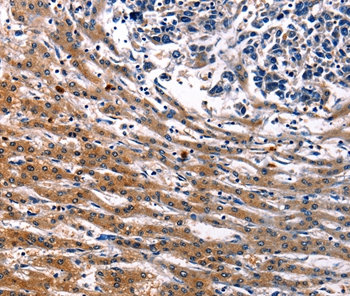

Immunohistochemical analysis of paraffin-embedded Human liver cancer tissue using #36935 at dilution 1/15.

Immunohistochemical analysis of paraffin-embedded Human breast cancer tissue using #36935 at dilution 1/15.